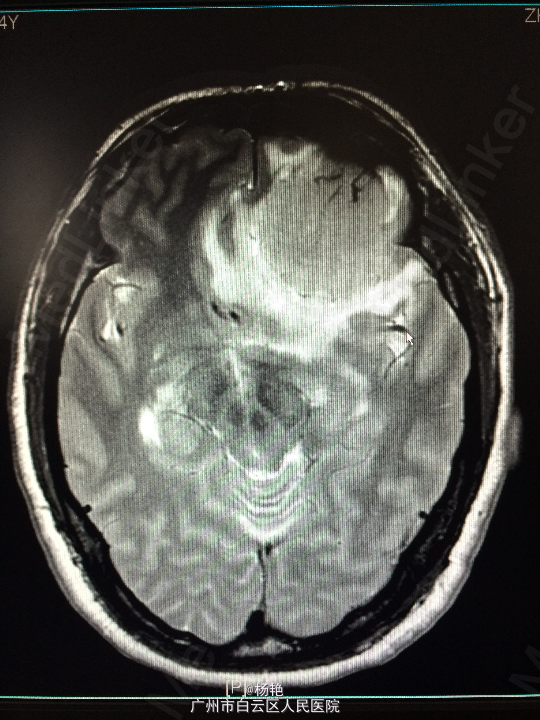

主诉:反复头痛2年加重1周 病史:患者诉两年前无明显诱因反复出现头晕头痛不适,近一周来症状加重,无恶心呕吐、无行走不稳、肢体乏力、意识障碍等。遂至当地医院诊治,行头颅CT、MR检查均提示颅内占位,良性可能性大,考虑脑膜瘤。今患者为求进一步治疗而入我院。

查体:神经系统查体未见明显异常 辅助检查:头颅MR提示:左侧额叶区域较大类圆形肿物,多考虑脑膜瘤可能;大脑前动脉及中动脉受压,中线偏移。

诊断:左额叶脑膜瘤 处理:在静脉全麻下行左侧额底脑膜瘤切除术,术后病理提示:脑膜瘤